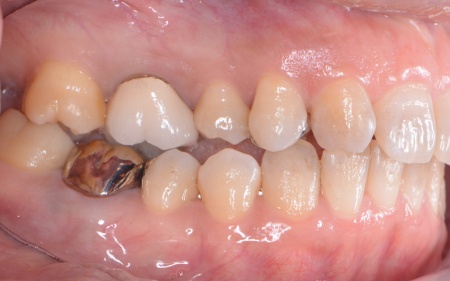

拝見したところ、左下奥歯(第1大臼歯)は以前、歯根分割処置が行われていました。

歯根分割処置とは、歯周病や虫歯などにより複数ある歯根のうちひとつだけがダメージを受けた場合に施す外科的な治療法です。

特に根が複数ある大臼歯に対して行われ、問題のある歯根のみを分割して抜くため残りの健康な歯根を残すことが可能です。

しかし残していた歯根の状態も悪化しており、治療しても温存は困難と判断しました。

左下奥歯はこのまま放置すると細菌感染を引き起こすため抜歯が必要なこと、抜歯後に歯を補うため人工歯根を利用したインプラント治療を提案し、同意いただきました。